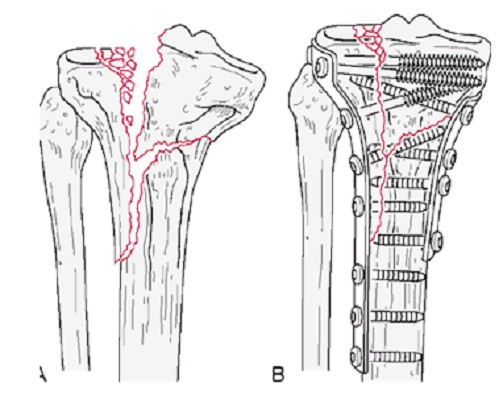

Significantly displaced tibial plateau fractures are usually treated by internal fixation.

The subtle depressed fractures can be treated arthroscopically with percutaneous placement of screws.